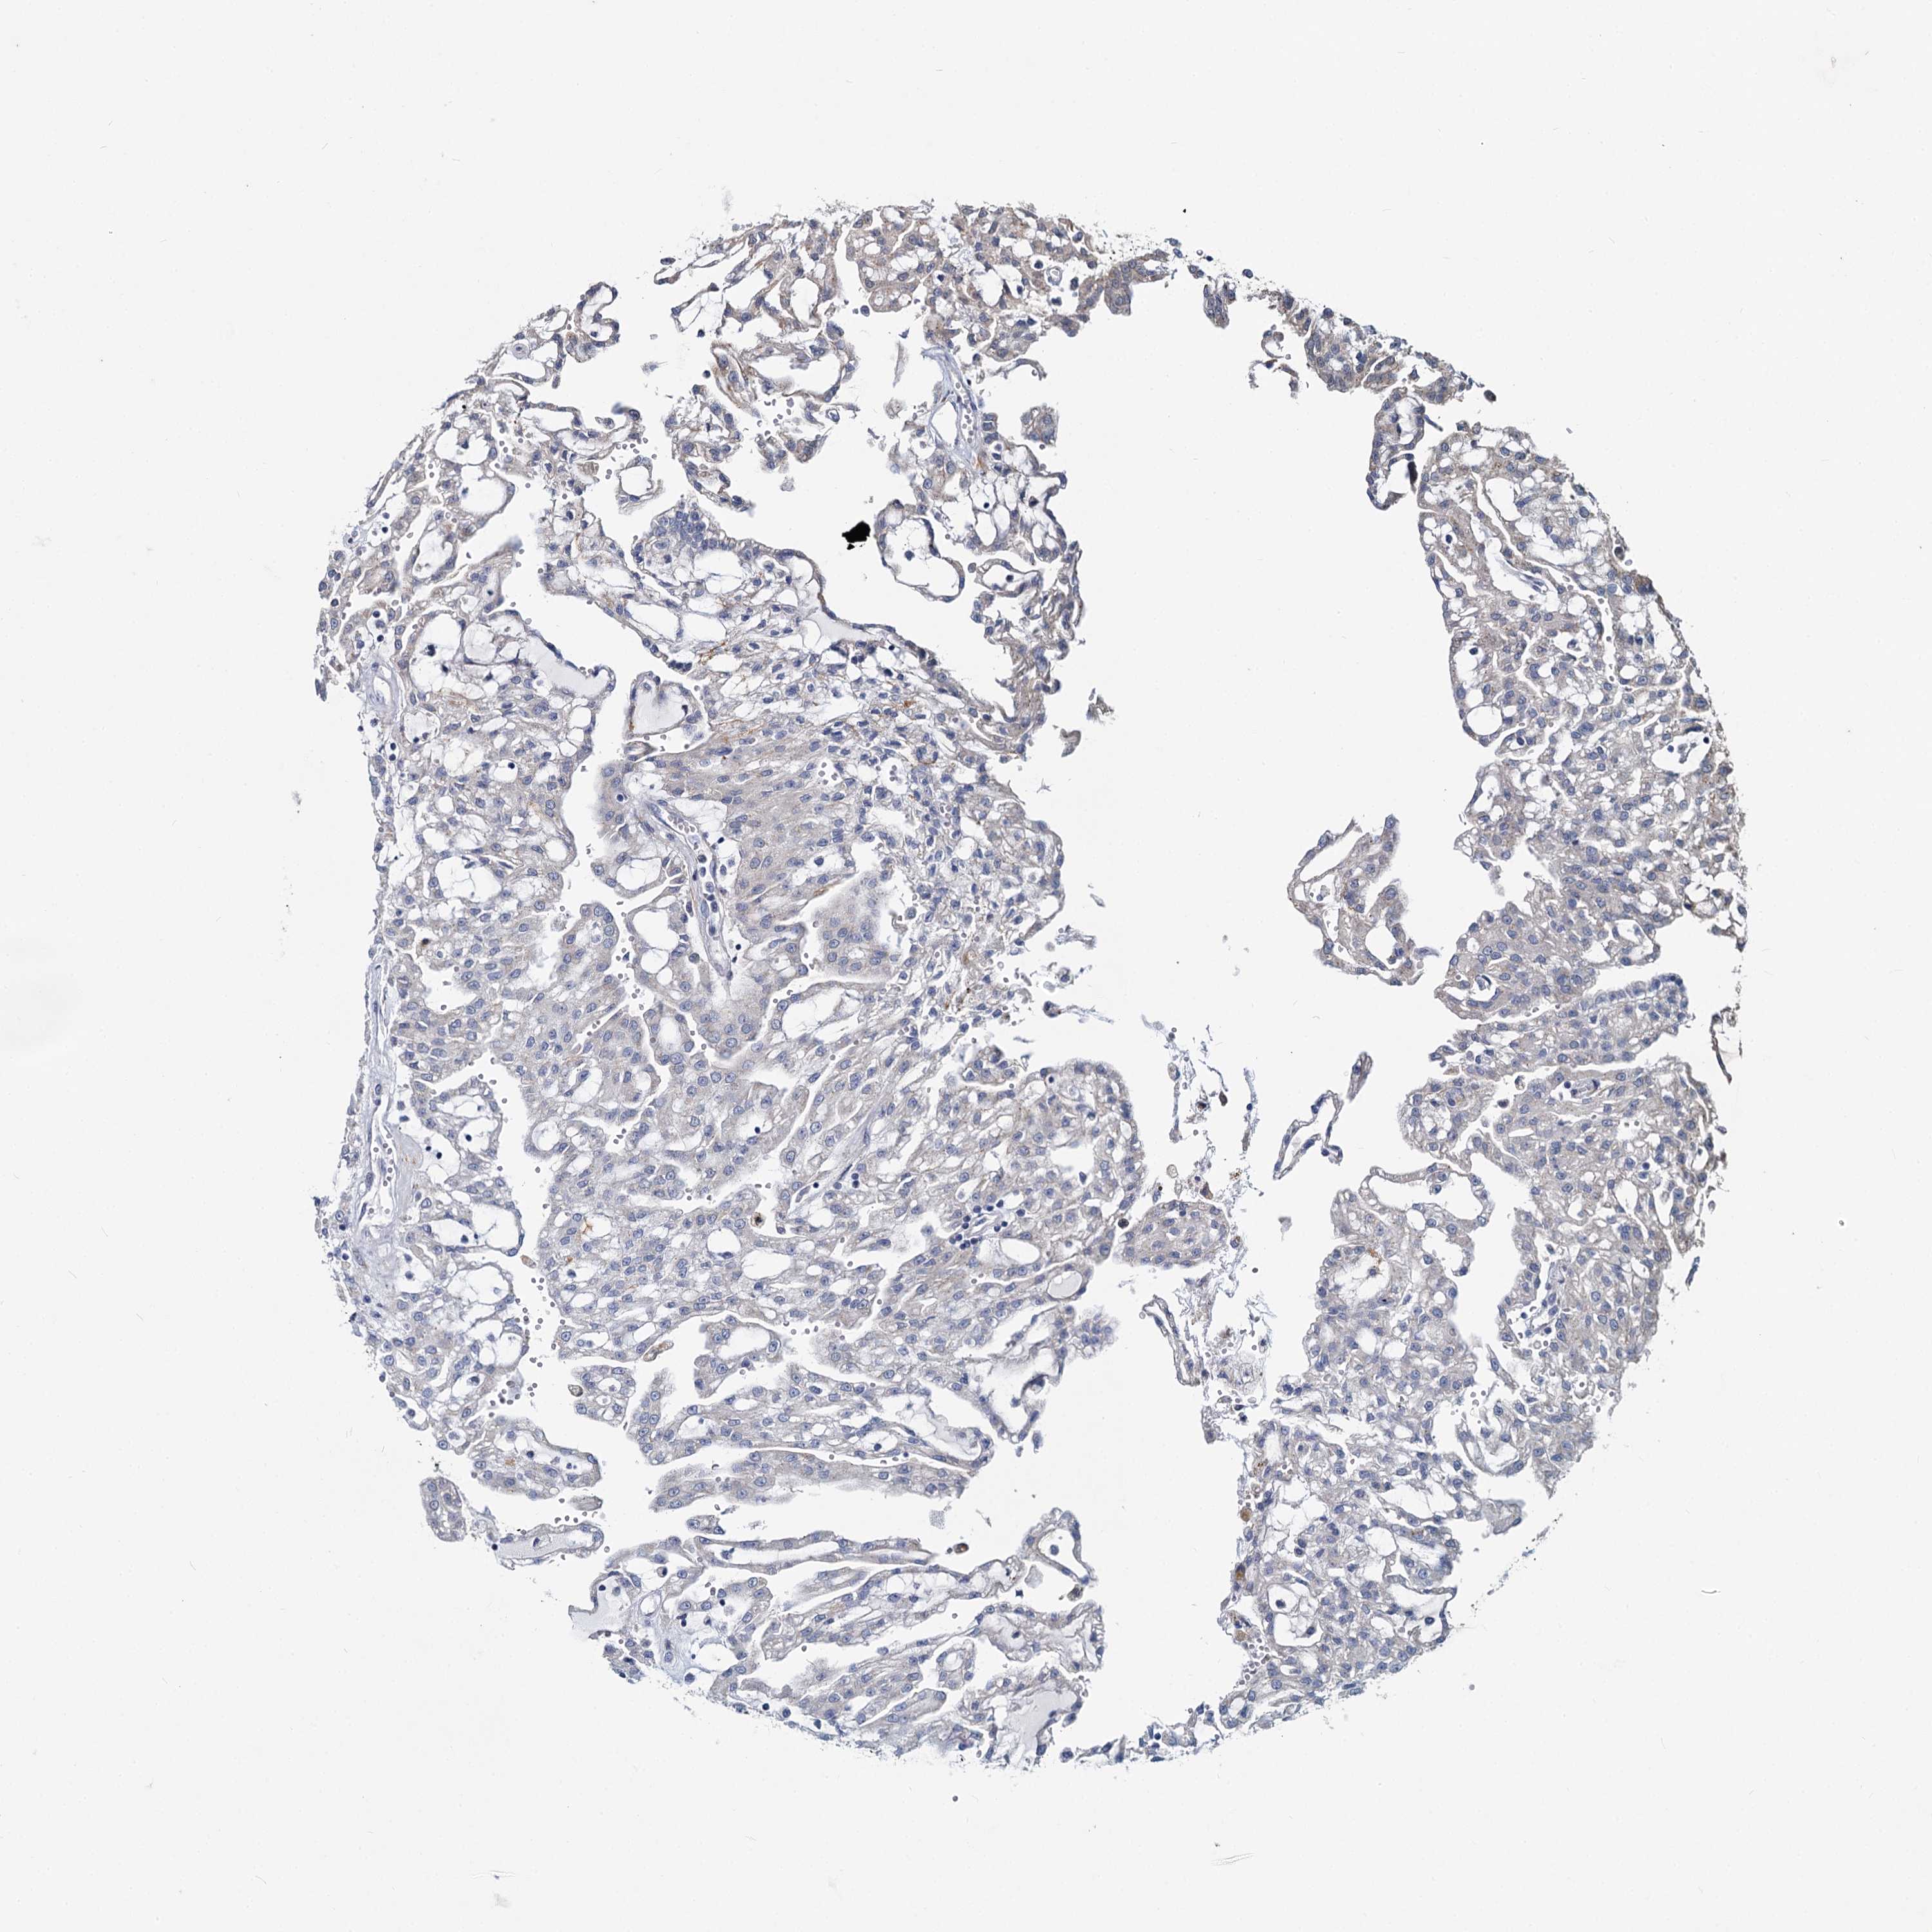

DCUN1D2

• CANCER

CANCER RENAL CANCER Show tissue menu

Renal cancer